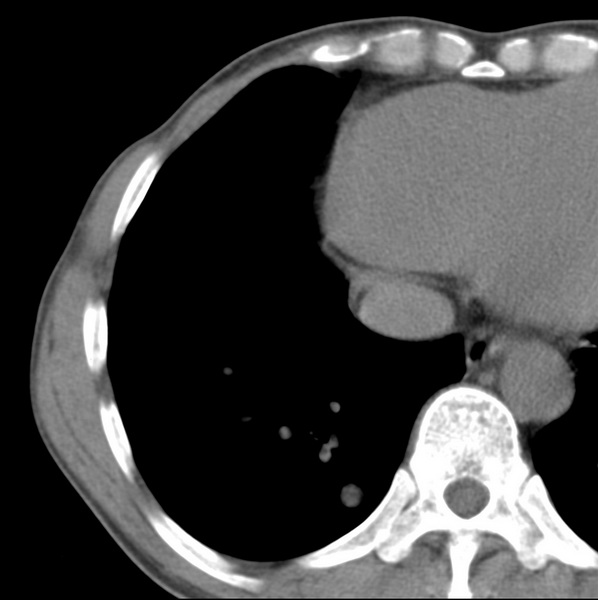

男、48、咳嗽。

胸片示双肺纹理紊乱,行胸部ct检查。

右肺下叶基底段结节影,双肺粟粒样阴影,ct值测量约-20hu左右,可能不准。

层厚层距为4mm左右,病灶轴面最大径约1cm左右。